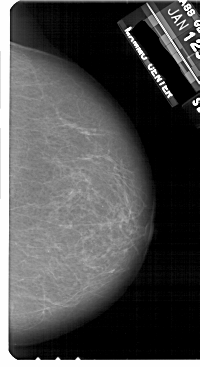

A_1812_1.LEFT_MLO

LEFT_MLO LINES 5206 PIXELS_PER_LINE 2821 BITS_PER_PIXEL 12 RESOLUTION 43.5 OVERLAY